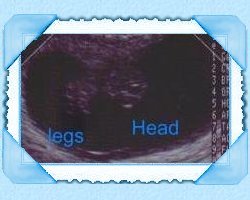

The second ultrasound we have had.

This is so neato our baby has legs i can see.. giggle.

As you can tell I marked the ultrasounds so you can tell :)